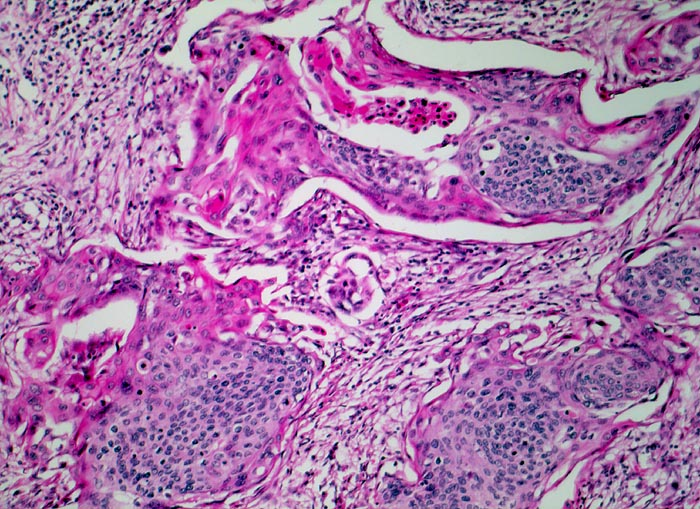

g/ Plattenepithelkarzinom der Zervix

Plattenepithelkarzinom der Zervix

Die Tumorzellen liegen einzeln oder in kleinen Verbänden und ganzen Gewebsfragmenten. Die polymorphen Kerne sind vergrössert und enthalten verklumptes unregelmässig verteiltes Chromatin und grosse Nukleolen. Gut differenzierte Karzinome erkennt man am breiten und oft verhornten Zytoplasma. Längliche bis fadenförmige Tumorzellen mit pyknotischen Kernen können als einziger Hinweis auf das Vorliegen eines Karzinoms vorhanden sein. Wenig differenzierte Karzinome haben polymorphe und schlechter erhaltene Kerne. Der Hintergrund ist meist detritisch und oft hämorrhagisch. Ulzeration, Einblutungen und bakterielle Infektionen beeinflussen den Erhaltungszustand und die Art der abgestrichenen Zellen. Ist die Oberfläche eines ulzerierten Karzinoms von einem Fibrinschorf bedeckt, enthalten die Ausstriche lediglich Detritus, Granulozyten und Erythrozyten, aber keine Tumorzellen. Die Sensitivität für die Karzinomdiagnose ist aus diesem Grund geringer als für die Diagnose eines Carcinoma in situ.